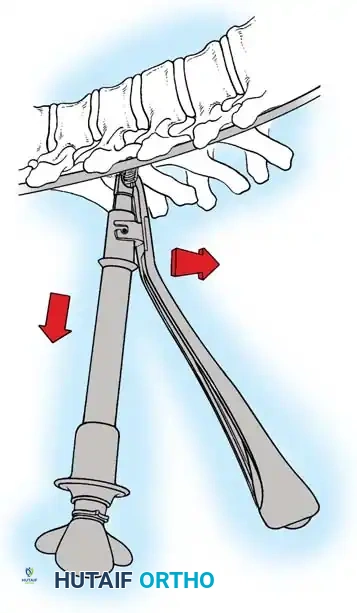

The Hall Technique

The Hall technique offers an alternative method for facet obliteration and grafting, particularly useful in rigid deformities.

Fig. 38-28: The Hall technique of facet fusion, involving sharp excision of the inferior facet and trough creation.

- Sharply amputate the inferior articular facet with a gouge and remove the bone fragment entirely. This exposes the cartilage of the superior facet.

- Remove the exposed cartilage completely with a sharp curet.

- Create a bleeding trough by removing the outer cortex of the superior facet.

- Impact cancellous bone grafts directly into this vascularized trough.

- Complete the procedure with global decortication of the posterior elements.